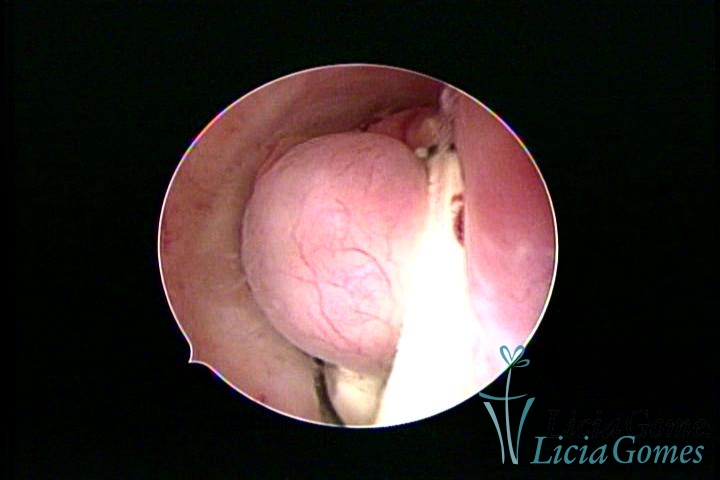

Dispositivo Mirena® e um mioma submucoso

×